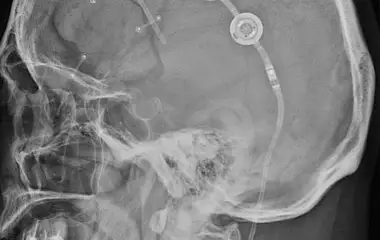

Der Bereich Hydrozephalus, Chiari-Malformation und Tethered-Cord-Syndrom umfasst die Diagnostik und Behandlung komplexer Erkrankungen des Liquorsystems sowie des Gehirns und Rückenmarks. Wir behandeln angeborene und erworbene Formen des Hydrozephalus, einschließlich des Normaldruckhydrozephalus, der sich häufig durch Gangstörungen, kognitive Veränderungen und Blasenfunktionsstörungen äußert. Ein weiterer Schwerpunkt ist die Chiari-Malformation, bei der es zu einer Verlagerung von Kleinhirnanteilen in den Spinalkanal kommen kann und die vielfältige neurologische Symptome verursachen kann. Das Tethered-Cord-Syndrom beschreibt eine krankhafte Fixierung des Rückenmarks, die sowohl in klassischer als auch in okkulter Form auftreten und zu Schmerzen, neurologischen Defiziten oder Funktionsstörungen führen kann. Ziel unserer Behandlung ist es, neuralen Strukturen zu entlasten, eine weitere Schädigung zu verhindern und die Lebensqualität der Patientinnen und Patienten zu verbessern. Grundlage hierfür sind eine präzise Diagnostik, individuell abgestimmte Therapiekonzepte und eine umfassende, verständliche Aufklärung.

Bei Hydrozephalus bieten wir verschiedene Formen der Liquorableitung an, darunter den Liquorshunt und den ventrikuloperitonealen Shunt (VP-Shunt), individuell angepasst an die jeweilige Erkrankung. Als alternative, shuntunabhängige Therapie führen wir die endoskopische Drittventrikulozisternostomie (ETV) durch, sofern die anatomischen Voraussetzungen gegeben sind. Patientinnen und Patienten mit Arnold-Chiari-Malformation behandeln wir durch eine gezielte mikrochirurgische Dekompression, um den Liquorfluss zu verbessern und neurologische Symptome zu lindern. Beim Tethered-Cord-Syndrom, einschließlich okkulter Formen, setzen wir auf ein minimalinvasives Detethering zur schonenden Entlastung des Rückenmarks.